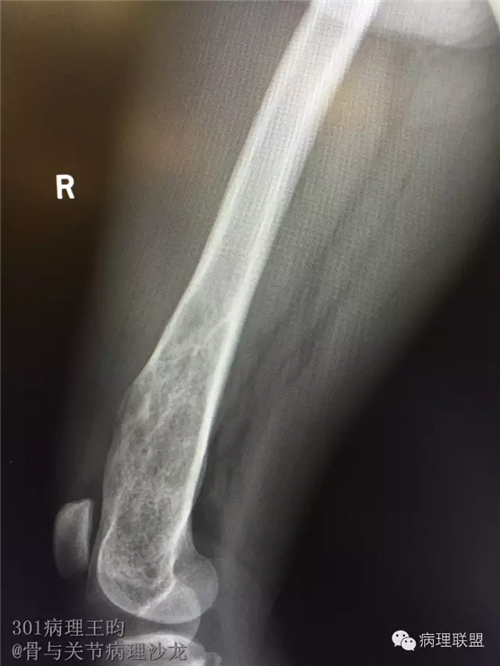

右股骨髓内高分化低级别骨肉瘤or骨纤维异常增殖症(Fibrous Dysplasia)?

男,36岁,活动后疼痛,发现右股骨远端肿瘤。